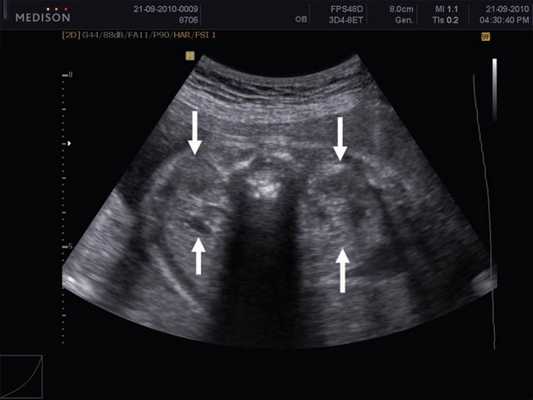

В представленном клиническом наблюдении диагноз опухоли почки был поставлен нами практически сразу и не вызывал сомнения, поскольку стандартный протокол ультразвукового скринингового исследования во II и III триместрах беременности требует описания почек и мочевого пузыря. Почки оцениваются в поперечном и продольном сечениях с использованием при необходимости цветового допплеровского картирования (рис. 3, а, б). В данном случае почки плода располагались в типичном месте, но обращали на себя внимание значительная разница в размерах и необычная структура одной из почек (см. рис. 1). В 2D режиме границы опухоли четко не визуализировались, но при использовании технологии VCI (объемное контрастное изображение) можно было более точно определить ее контуры (рис. 4).

Рис. 3. Исследование почек.

а) Поперечное сканирование. Переднезадний размер почек обозначен стрелками.